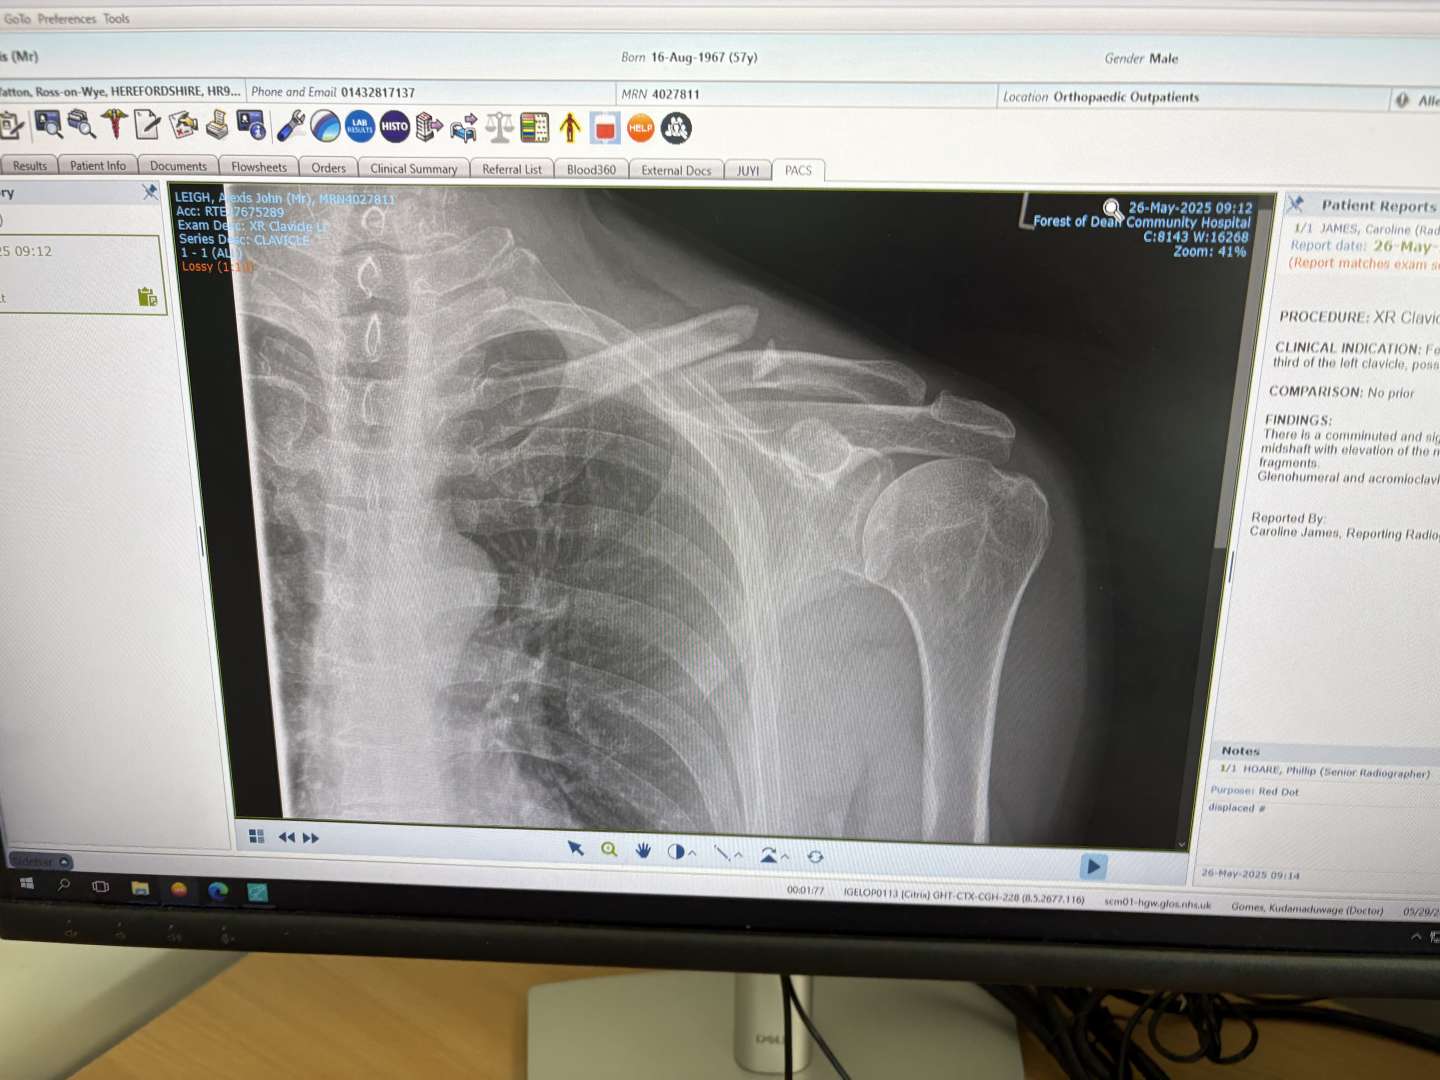

So I had proper over the bars, landed on my back and broke my collarbone. It's a pretty big separation, so been referred to fracture clinic. It looks like it's broken where the bone was a bit thin because of a previous injury that chipped a fragment off. I'm 56 so it's unlikely to re-join (as opposed to if I was 5.6 😉 )

Update time: went to see a consultant at the Nuffield and his view was it'd heal as strong as it was but it could take up to 12 months 🙁 Probably closer to 8 as his view was I was doing everything right to aid recovery. The reason given was not the severity of the injury but the way I did it- ie lots of trauma=longer healing times. Apparently big difference between falling off a curb and planting yourself into some rock hard soil at some velocity.

Cost of private op is 9k ish. Recovery time would be 4-6 weeks. His view was also fracture clinic would just keep kicking it down the road as it's elective surgery (in line with some experiences in this thread). I've missed the 'first" window to have any op, next one would be after 8 weeks. So that's 6 weeks to make a decision I guess.